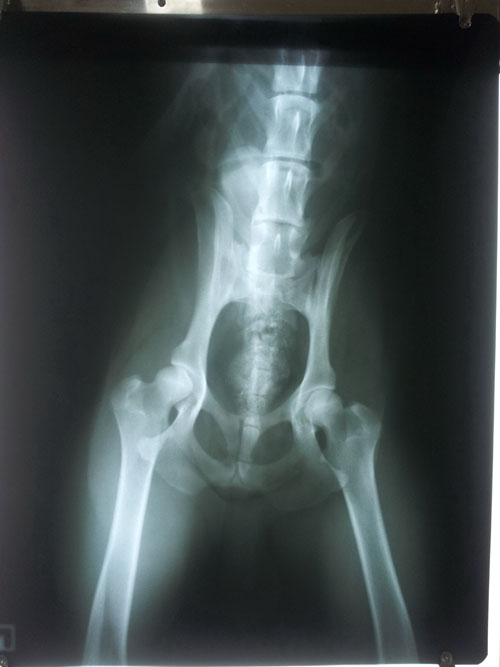

HD - Normal